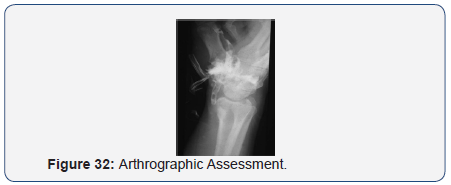

Arthrographic assessment

- Isolated.

- Communications-

- Midcarpal

- Radiocarpal

- Radioulnar

- Tendon Sheaths

- Pouch between 1st & 2nd metacarpal bases